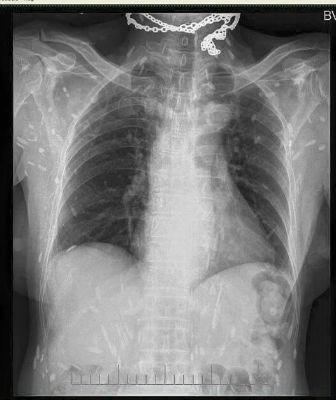

Rùng mình trước hình X - quang của người mê... ăn sống

Mấy ngày gần đây, cộng đồng mạng chia sẻ các bức ảnh chụp X-quang rất khủng khiếp của một bệnh nhân nhiễm sán. Theo đó, trên các bức ảnh X-quang là la liệt các xác sán xơ mít có đầu vôi hóa hình như hạt gạo. Theo các bác sĩ, nguyên nhân bị nhiễm sán là do ăn phải thức ăn sống như rau sống, tiết canh, gỏi cá… có nhiễm trứng, ấu trùng sán.

Nhiễm sán vì mê thức ăn sống

Sau khi bức ảnh được đưa lên, rất nhiều người cảm thấy sợ hãi và không khỏi rùng mình.

Bác sĩ Lương Quốc Chính - Bệnh viện Bạch Mai cho biết: “Rất nhiều người vẫn cho rằng đây không phải là hình ảnh của nhiễm sán vì không thể có chuyện sán lại cản quang trên phim X-quang được, nhưng vì đây là tổn thương đã vôi hóa nên mới cản quang như vậy, chỉ cần sử dụng hai từ khóa Cysticercosis, Trichinellosis để tìm ảnh trên trang tìm kiếm google sẽ thấy những hình ảnh tương tự”.